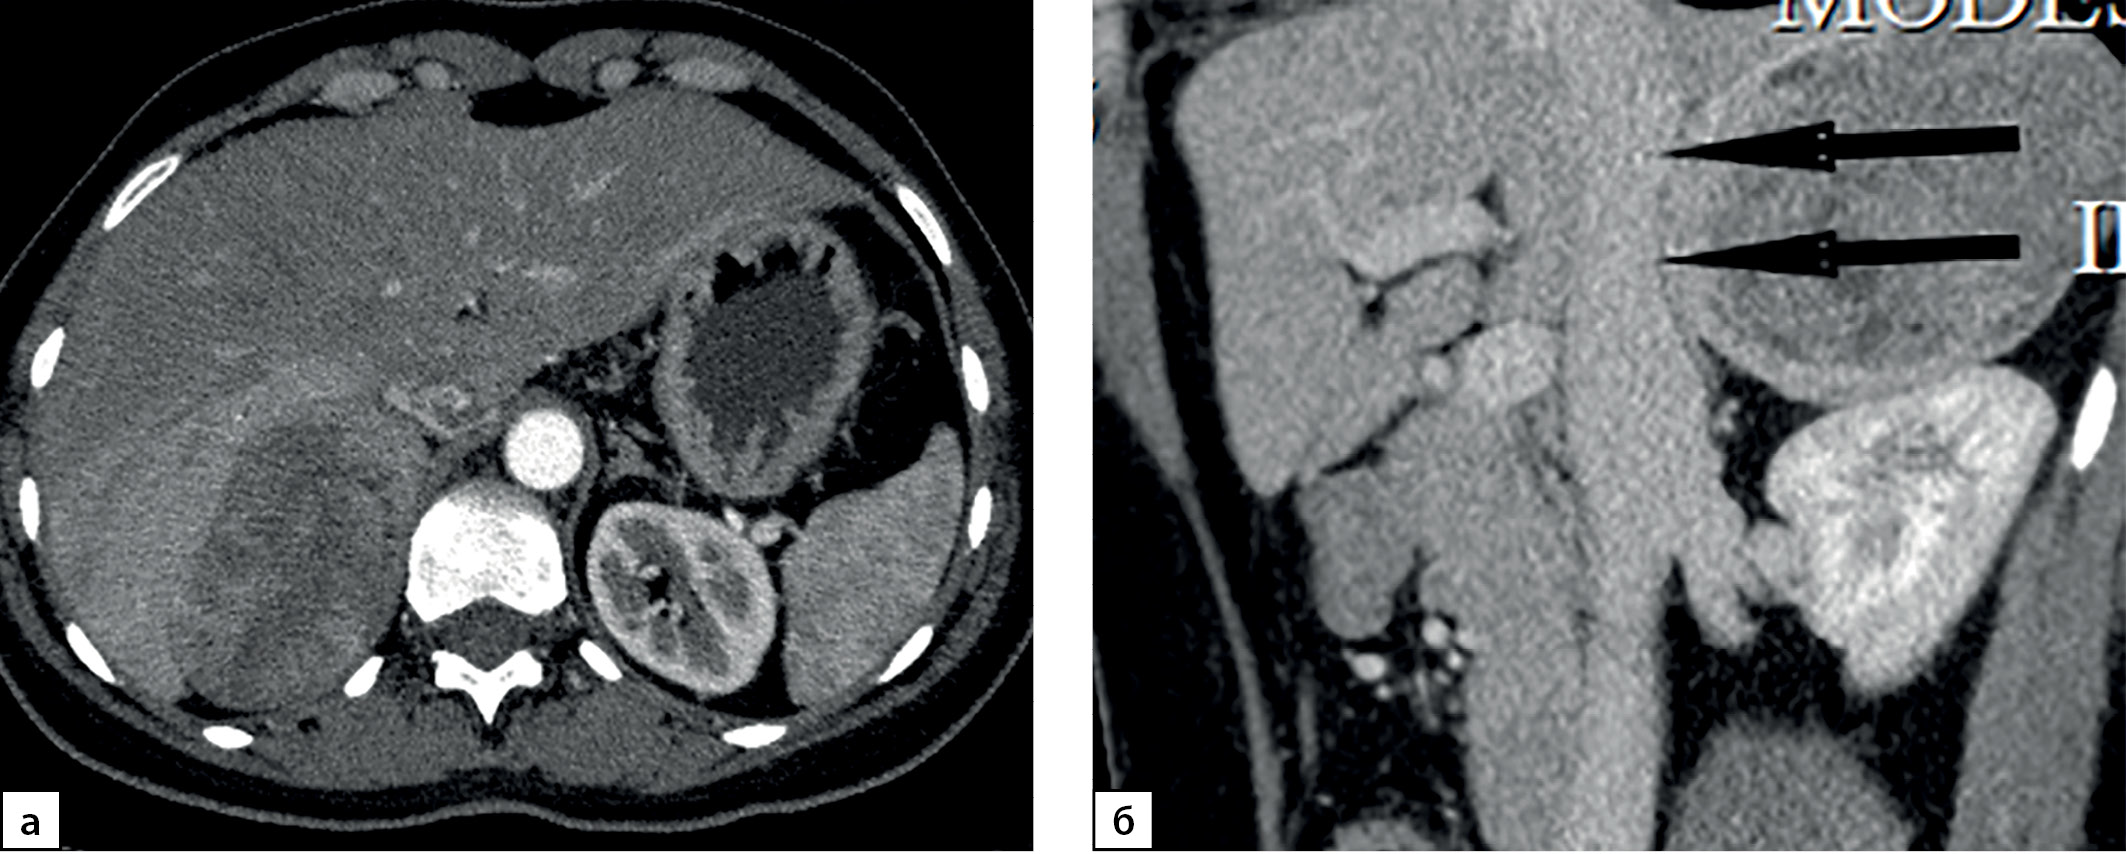

Размер опухолей в группе больных с первично выявленным АКР составлял 7,05 (5,85–7,67) см при минимальном значении 3 и максимальном — 23 см. Данные о размерах новообразований представлены на рис. 1. Злокачественные адренокортикальные опухоли мы условно разделили в зависимости от размера на маленькие до 4 см (6 случ.), средние от 4 до 6 см (11 случаев), большие от 6 до 10 (41 случай) и гигантские (рис. 2) — более 10 см (12 случай). Следует заметить, что от размеров опухоли зависит выбор хирургического подхода: при опухолях небольшого размера без инвазии или лимфаденопатии выполнялась ретроперитонеоскопическая адреналэктомии, при наличии метастазов в регионарные лимфоузлы, инвазии ворганы и сосуды или крупной опухоли — открытая адреналэктомия. Особое внимание обращает на себя категория пациентов (8,6% наблюдений), имеющих малые размеры образования (от 3 до 4 см). Их, в силу небольших размеров, в клинической практике обычно не рассматривают с позиции онкологической настороженности, а именно в этой группе существует наибольшая вероятность несвоевременной диагностики злокачественной опухоли (рис. 3, 4).

Рисунок 3. Компьютерные томограммы пациентки И., 67 лет с малыми размерами адренокортикальной карциномы (28х35 мм), распространяющейся из латеральной ножки левого надпочечника вдоль передней поверхности почки: а — изображение в аксиальной плоскости, нативная фаза сканирования — показатели плотности до 16 HU; б — артериальная фаза постконтрастного сканирования; в — венозная фаза; г — фаза отсроченного сканирования, коэффициент абсолютного вымывания контрастного препарата составил 42%, относительного — 31,8%.

Figure 3. Computed tomography of patient I., 67 years old, with small size adrenocortical carcinoma (28x35 mm), spreading from the lateral pedicle of the left adrenal gland along the anterior surface of the kidney: a — image in the axial plane, native scanning phase — density values up to 16 HU; b — arterial phase of post-contrast scanning; c — venous phase; d — phase of delayed scanning, the coefficient of absolute washout of the contrast agent was 42%, relative — 31.8%.

Рисунок 4. Компьютерные томограммы пациентки Ч., 42 лет с небольшой адренокортикальной карциномой (32х28 мм), с гетерогенной опухолевой тканью, распространяющейся до ворот почки: а — изображение в аксиальной плоскости, нативная фаза сканирования, плотность от +8,4 до +38HU; б — артериальная фаза постконтрастного сканирования; в — венозная фаза; г — фаза отсроченного сканирования, д — изображение реформатированное в косой сагиттальной плоскости, венозная фаза сканирования, образование локально деформирует почечную вену (стрелка). Коэффициент абсолютного вымывания контрастного препарата составил 56%, относительного — 36%.

Figure 4. Computed tomography of patient Ch., 42 years old, with a small adrenocortical carcinoma (32x28 mm), with heterogeneous tumor tissue extending to the hilum of the kidney: a — image in the axial plane, native scanning phase, density from +8.4 to +38HU ; b — arterial phase of post-contrast scanning; c — venous phase; d — phase of delayed scanning, e — image reformatted in the oblique sagittal plane, venous phase of scanning, the mass locally deforms the renal vein (arrow). The coefficient of absolute washout of the contrast agent was 56%, relative — 36%.